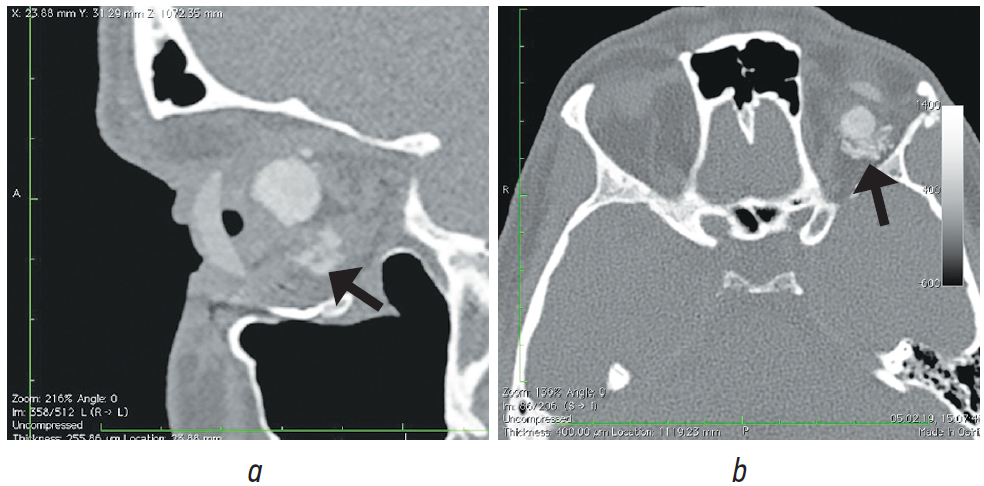

Рис. 8. Пациент, 21 год. 2,5 года после операции с имплантацией эндопротеза с изменённой геометрией. МСКТ-исследование

Fig. 8. Patient, 21 y. o. 2,5 years after surgery with implantation of an endoprosthesis with modified geometry. MSCT of the socket

При анализе рентгенологических изображений после выполнения МСКТ-диагностики у всех обследованных пациентов по описанному ранее алгоритму [16] нами было выявлено изменение размеров и геометрии орбитальных сфер в виде «срезанной» части (рис. 8). Параметры изменённой части, как и размеры самих имплантатов, были различны (табл. 1–3). Исходные параметры (диаметры) орбитальных сфер — 18, 19 и 20 мм. При компьютерно-томографическом исследовании на полученных изображениях мы анализировали размеры имплантированных материалов, определяя объём вкладышей через радиус и высоту срезанной части по формуле: V = 1/3πh2(3r – h), где π — константа, равная 3,14; r — радиус шара; h — высота шарового сегмента имплантата.

Анализируя полученные данные, мы установили, что размеры изменённой геометрии имплантированных орбитальных вкладышей отличались, потери объёма при исходном диаметре 20 мм составили в среднем 0,4038 см3, при диаметре 19 мм — 0,340 см3, при диаметре 18 мм — 0,298 см3 (рис. 7–11).

В мягких тканях вокруг изменённых имплантированных сфер нами выявлены уплотнения, без признаков кальцинации и деструкции стенок орбиты (рис. 7, 8). Кроме того, у одной пациентки было отмечено не только изменение геометрии сферы в виде срезанной части (рис. 10, а), но и наличие множества фрагментов полимерного материала идентичной рентгенологической плотности. Эти фрагменты имплантата находились за задним полюсом полимерного вкладыша в мягких тканях до вершины орбиты (рис. 10, b).